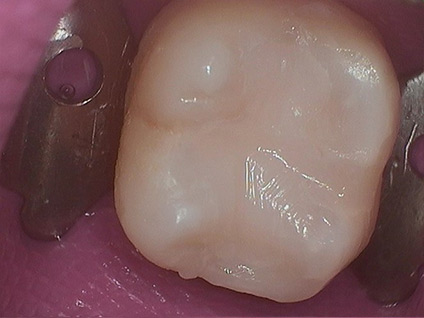

3. Decay Removed

4. Tooth is Restored